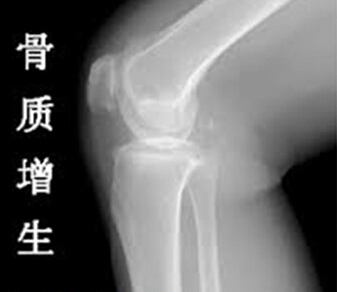

骨质增生关节炎怎么治疗

导读:骨质增生关节炎又称退行性骨关节病。由于老年人内分泌紊乱使骨关节发生退行性变、关节软骨退变、断裂、甚至脱落、软骨下骨质增生,骨刺形成,引起关节疼痛、活动不利、功能障碍等。

骨质增生关节炎又称退行性骨关节病。由于老年人内分泌紊乱使骨关节发生退行性变、关节软骨退变、断裂、甚至脱落、软骨下骨质增生,骨刺形成,引起关节疼痛、活动不利、功能障碍等。本病的发展缓慢,呈隐袭性,多在40岁以后出现症状。>>>点击了解更多骨质增生关节炎,让专家为您答疑解惑。